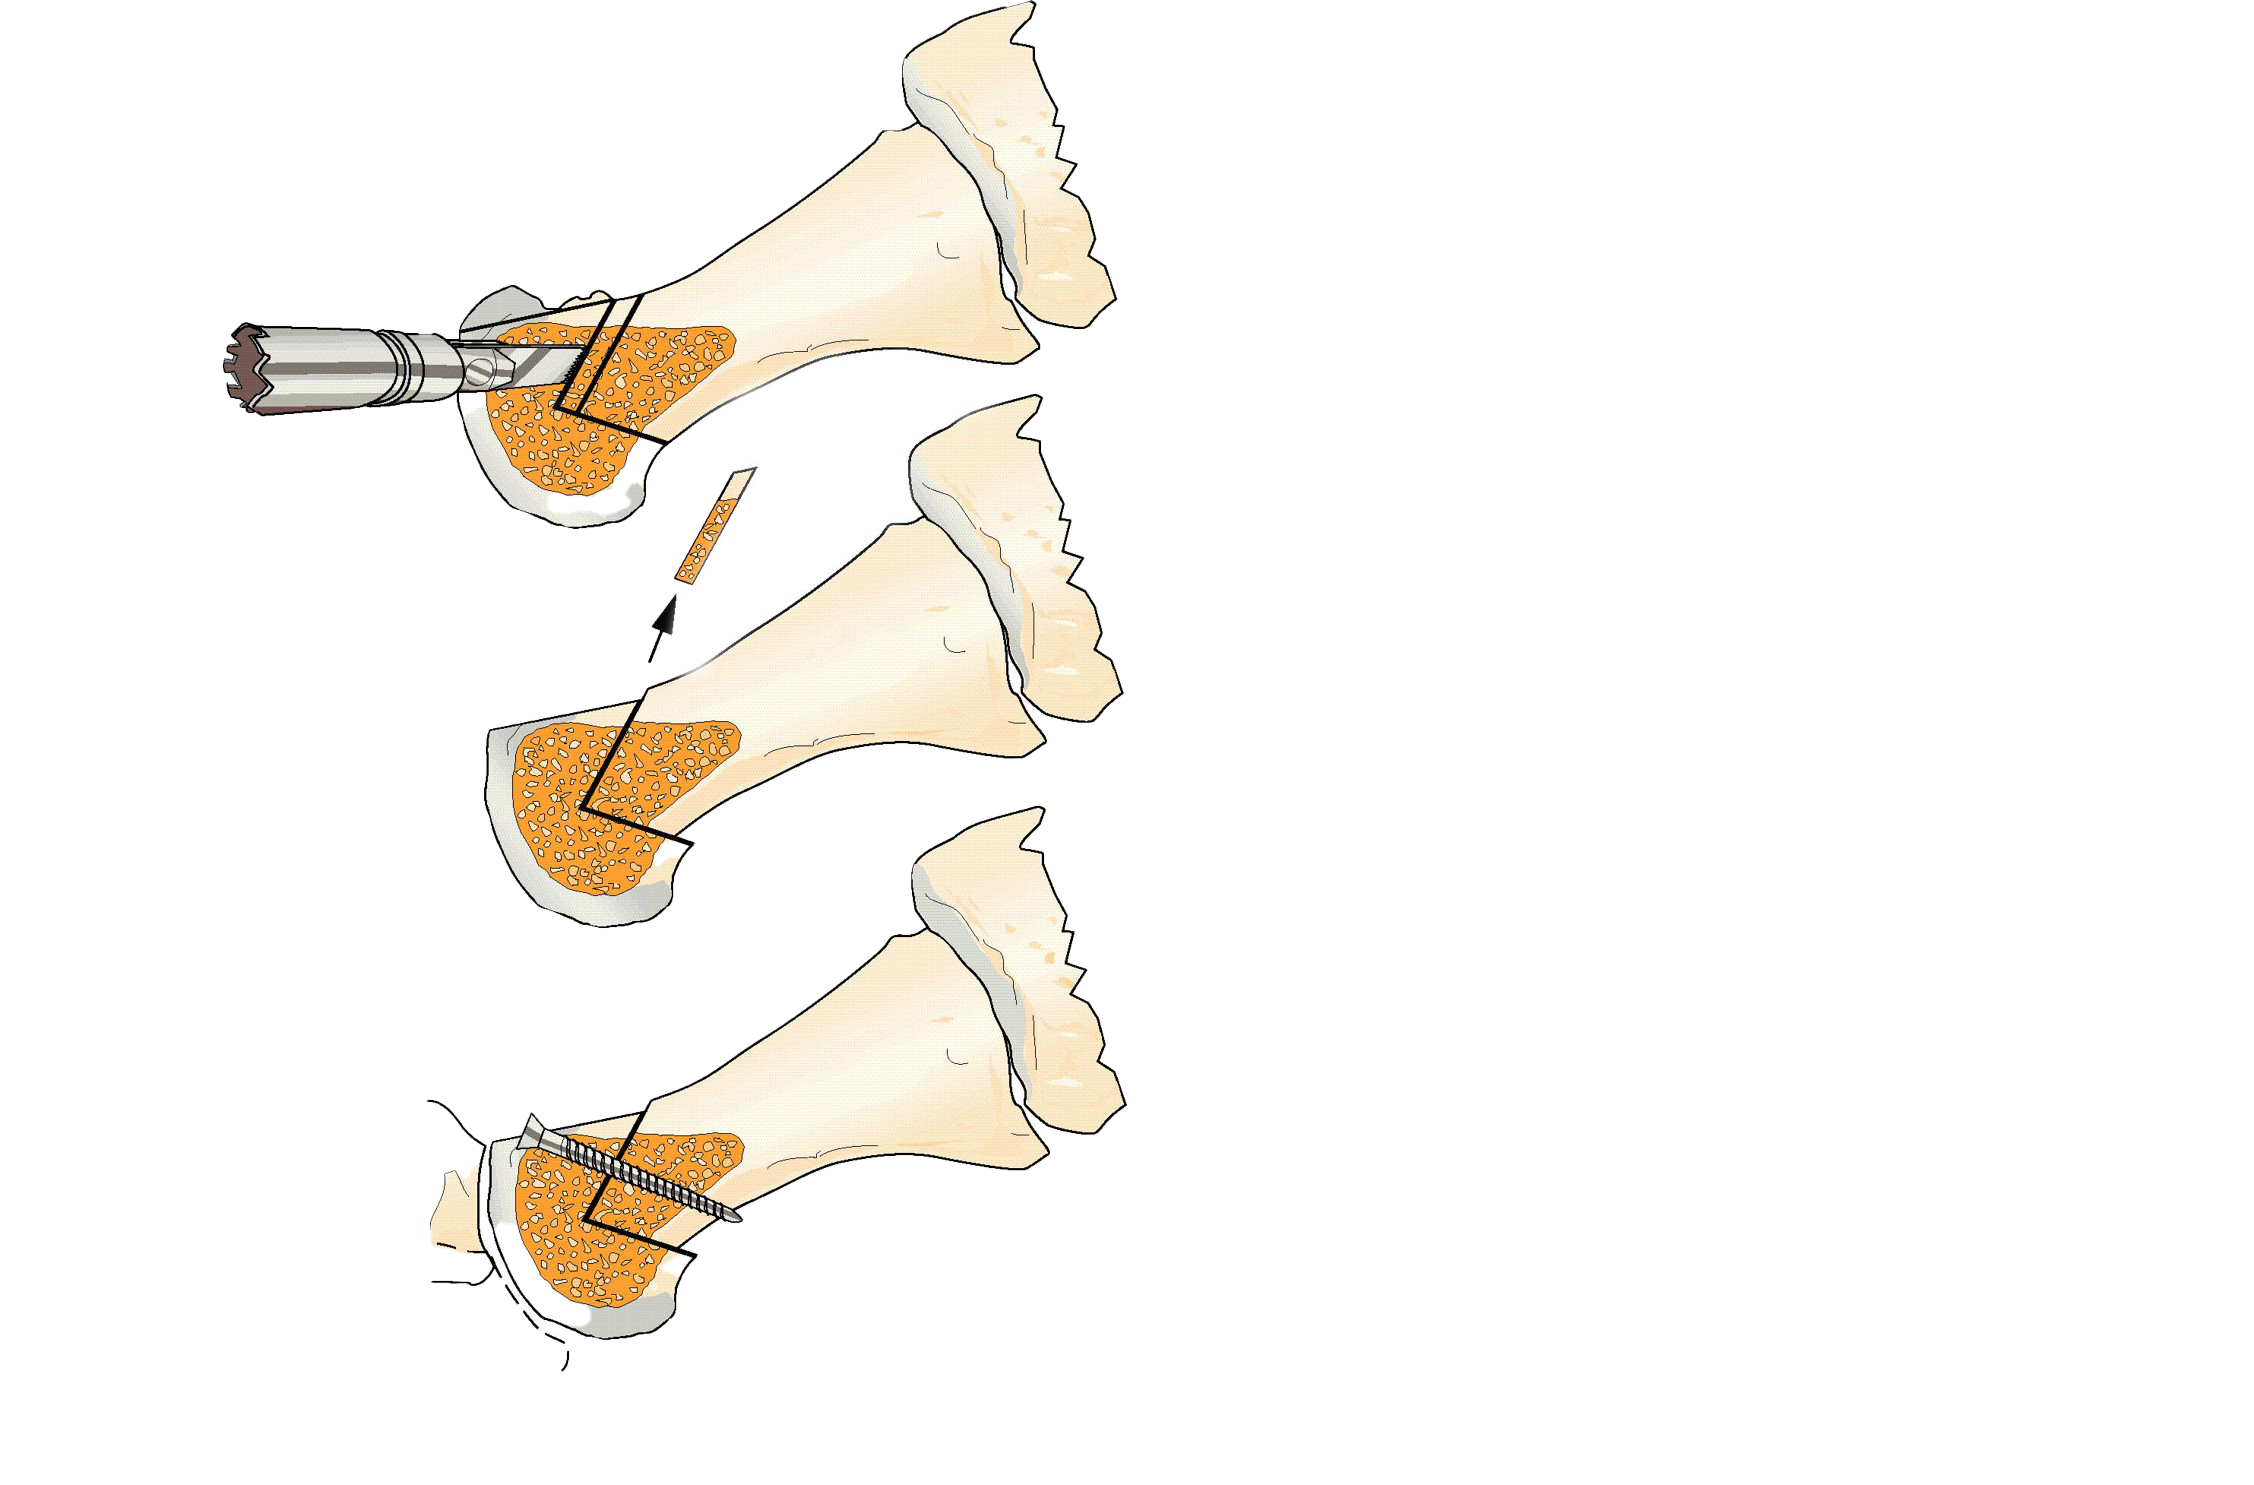

Kirurgisk behandling

När kirurgisk behandling är indicerad rekommenderas tre operationsmetoder beroende på grad av artros, patientens besvär och individuella behov [12][13]

- förkortningsosteotomi

Förkortnings-osteotomi |

En variant av chevron osteotomi (Youngswick) där metatarsalbenet förkortas. Fixering med skruvar. Utförs vanligtvis tillsammans med mobilisering av leden och borttagning av osteofyter. |

≤ Grad 3. |

Förkortningsosteotomi |

Behandlingssko under 6 veckor, vilket möjliggör belastning. (24) Rörelseträning bör inledas tidigt. |